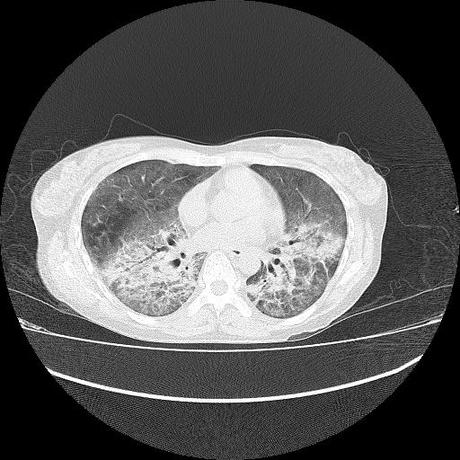

El parénquima pulmonar con areas parcheadas difusas en vidrio despulido combinadas con otras areas hipodensas de baja atenuación debidas a atrapamiento aéreo y engrosamiento intersticial y zonas de fibrosis de predominio en lóbulos medios e inferiores de ambos pulmones.

- LOS HALLAZGOS PUEDEN ESTAR EN RELACIÓN A NEUMOPATIA INTERSTICIAL PROBABLE ETIOLOGIA HIPERSENSITIVA VS AUTOINMUNE/BACTERIANA/FUNGICA.